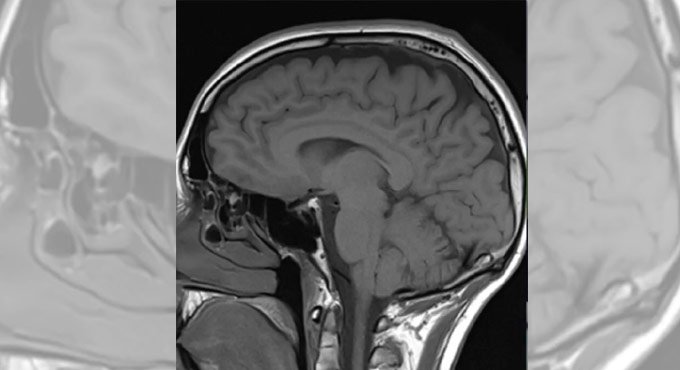

New York: A team of researchers has created a nanoparticle platform to facilitate successful delivery of therapeutic agents to the brain, which could open possibilities for the treatment of numerous neurological disorders.

Although researchers have in the past decade identified biological pathways leading to neurodegenerative diseases and developed promising molecular agents to target them, delivering therapeutics across the blood-brain barrier (BBB) and into the brain has been a challenge.

The newly created nanoparticle platform can facilitate therapeutically effective delivery of encapsulated agents in mice with a physically breached or intact blood-brain barrier, said the study published in the journal Science Avances.

In a mouse model of traumatic brain injury (TBI), they observed that the delivery system showed three times more accumulation in brain than conventional methods of delivery and was therapeutically effective as well.

The researchers believe that the study could open possibilities for the treatment of numerous neurological disorders.

Previously developed approaches for delivering therapeutics into the brain after traumatic brain injury rely on the short window of time after a physical injury to the head, when the blood-brain barrier is temporarily breached.

However, after the blood-brain barrier is repaired within a few weeks, physicians lack tools for effective drug delivery.

“It’s very difficult to get both small and large molecule therapeutic agents delivered across the BBB,” said corresponding author Nitin Joshi from Brigham and Women’s Hospital in the US.

“Our solution was to encapsulate therapeutic agents into biocompatible nanoparticles with precisely engineered surface properties that would enable their therapeutically effective transport into the brain, independent of the state of the BBB.”

The technology could enable physicians to treat secondary injuries associated with traumatic brain injury that can lead to Alzheimer’s, Parkinson’s, and other neurodegenerative diseases, which can develop during ensuing months and years once the blood-brain barrier has healed.